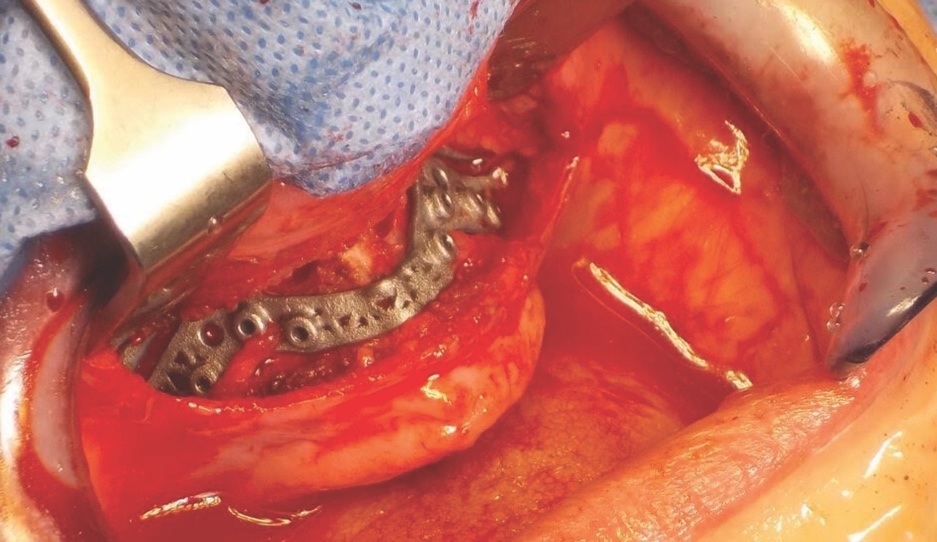

Following careful informed consent, the patient was treated in the OMFS Department in Ninewells Hospital. The first surgical stage was completed with a bimaxillary osteotomy with 3D guides and plates (KLS Martin) followed by bone grafts from the left iliac crest to the maxilla and mandible (Figure 5). The maxilla was advanced 10mm and set down 7mm.

The piezoelectric system was very important in the management of this patient. It was used to split the maxillary and mandibular ridges (UR4, UR1, LL3 and LR2 regions) and also to remove the bone and open the alveolar ridge anteriorly and posteriorly on the right side of the maxilla.

The novelty lies not solely in the tool, but in the context-specific application, the piezoelectric instrumentation in the osteotomy of an underdeveloped maxilla, which remains under-reported in the literature. This approach allowed cuts to be within a controlled small width and avoided unnecessary bone loss. It also minimised the risk of soft tissue injury. It was initially virtually planned that the patient would have one zygomatic implant placed on each side; however, unfortunately, due to limited zygomatic bone volume, it was felt intra-operatively that this was not appropriate. Instead, a ridge split was performed to allow placement of dental implants into the maxilla. Using the piezoelectric saw allowed for widening of the mandibular alveolar ridge without the risks associated with chisels and osteotomes. The precision and safety profile of piezoelectric instruments made it the essential tool in this situation, as its use was necessitated by the patient’s exceptionally thin maxillary bone. Conventional drills or chisels posed a significant risk of iatrogenic fracture or collateral damage to adjacent soft tissue structures and were therefore unsuitable in this case.